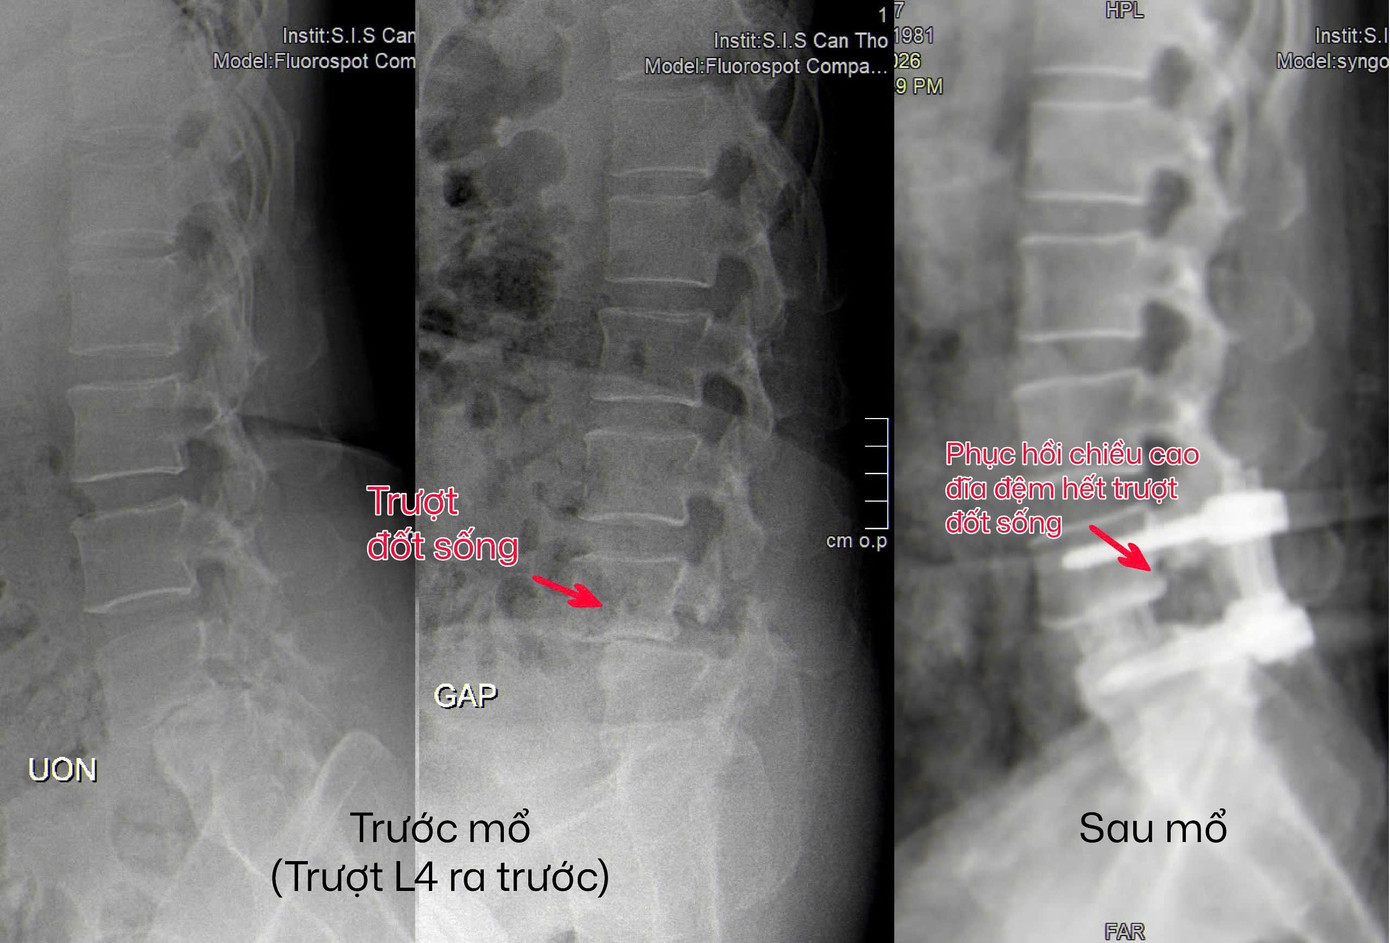

Vị trí trượt đốt sống thắt lưng gây ra những cơn đau dữ dội cho bệnh nhân (hình ảnh trước và sau mổ)

Trước diễn tiến bệnh ngày càng nặng, chị M. đã đến Bệnh viện Đa khoa Quốc tế S.I.S Cần Thơ thăm khám. Qua kiểm tra lâm sàng và chụp MRI 3T cột sống thắt lưng, các bác sĩ xác định chị bị trượt đốt sống mất vững. Đây là tình trạng các đốt sống bị lệch khỏi vị trí bình thường và không còn ổn định khi vận động.

“Ở bệnh nhân này, cột sống không còn ổn định, khi cúi thì đốt sống trượt ra trước, khi ưỡn thì khe giữa các đốt sống lại hở ra. Nếu chỉ giải phóng chèn ép thần kinh là chưa đủ mà cần phải tái lập sự vững chắc cho cột sống”, BS Hưng cho biết.

Trong ca mổ, ê kíp đã sử dụng hệ thống nội soi để giải phóng chèn ép thần kinh, loại bỏ phần đĩa đệm tổn thương và thực hiện ghép xương liên thân đốt. Một miếng ghép được đặt vào giữa hai đốt sống, kết hợp với xương tự thân và vật liệu hỗ trợ để thúc đẩy quá trình liền xương. Sau đó, cột sống được cố định bằng hệ thống vít qua da.